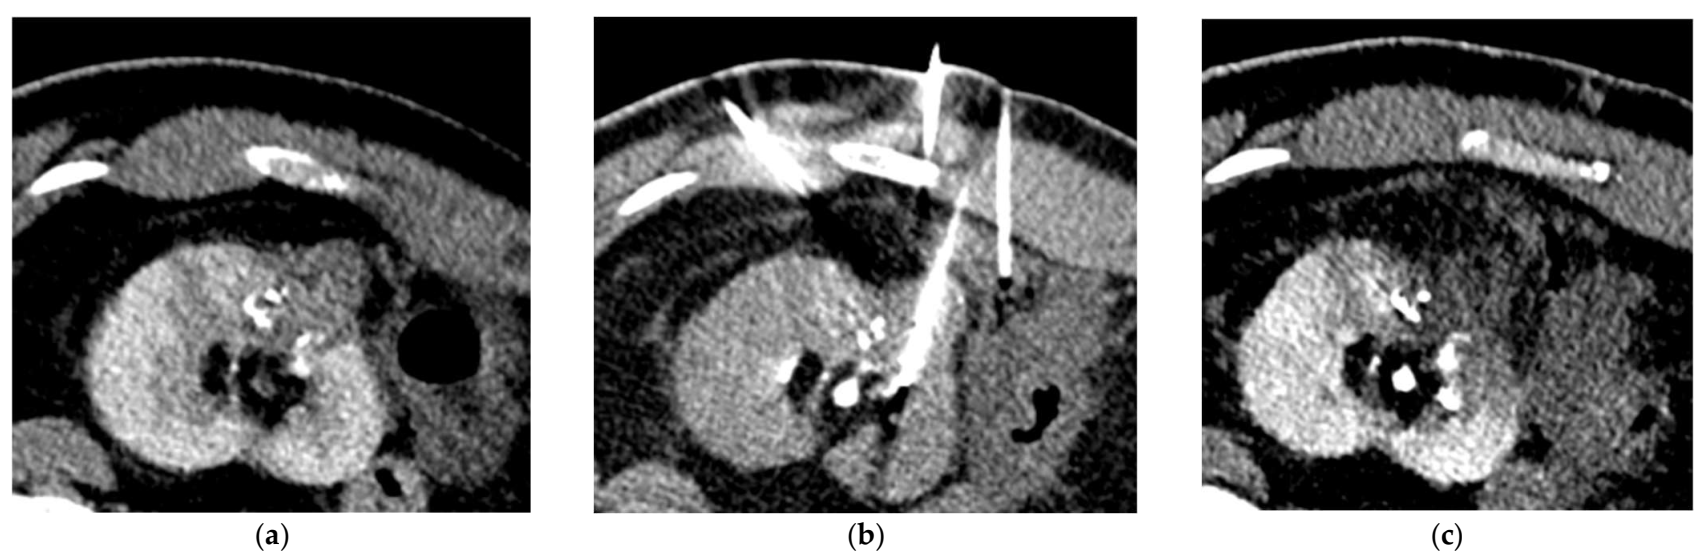

Table 4 reports the features of the PCA procedures. Complete ablation was obtained for all patients and no immediate complications were visible on the control unenhanced CT-scan performed at the end of the procedure. Five patients required hydrodissection prior to ablation. No patient reported more than moderate pain after PCA. No ice-ball cracking occurred. Figure 3 and Figure 4 show examples of PCA of renal cell carcinoma after SAE.

Figure 3.

CT-guided percutaneous cryoablation procedure of a renal cell carcinoma of the left kidney performed after selective arterial embolization using NBCA/Lipiodol® mixture. (a) Enhanced CT-scan for trajectory planification showing a complete devascularization of the tumor. Note the Lipiodol® uptake in the tumor area that can increase targeting accuracy. (b) Volume rendering reconstruction showing the cryoprobes placement. (c) Unenhanced control CT-scan post-ablation showing the optimal coverage of the tumor without any immediate complication.

Figure 4.

CT-guided percutaneous cryoablation procedure of a renal cell carcinoma of the left kidney performed after selective arterial embolization using NBCA/Lipiodol® mixture. (a) Enhanced CT-scan for trajectory planification showing a complete devascularization of the tumor with lipiodol uptake. Note that the left colon is really close to the kidney. (b) CT acquisition showing the hydrodissection technique with needle placement for injection of dextrose solution to repel the colon and protect it. (c) Unenhanced control CT-scan post-ablation showing the optimal coverage of the tumor without any immediate complication.